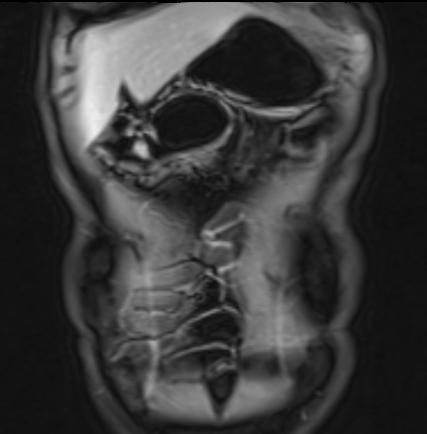

Hình ảnh T1W sau tiêm thuốc tương phản của bệnh nhân có khối thâm nhiễm lớn liên quan đến nhiều quai ruột non.

Thâm nhiễm

Thâm nhiễm có thể biểu hiện dưới dạng mỡ bò (creeping fat) xâm lấn giữa các quai ruột kèm thay thế tín hiệu mỡ bình thường, cùng với hiện tượng kéo dính và gập góc các quai ruột.

Các triệu chứng tắc nghẽn do dính ruột, hẹp do viêm hoặc xơ hóa là những biểu hiện thường gặp.

Rò và áp-xe thường đồng thời hiện diện.

Do cấu trúc phức tạp, đường đi chính xác của đường rò có thể khó xác định.